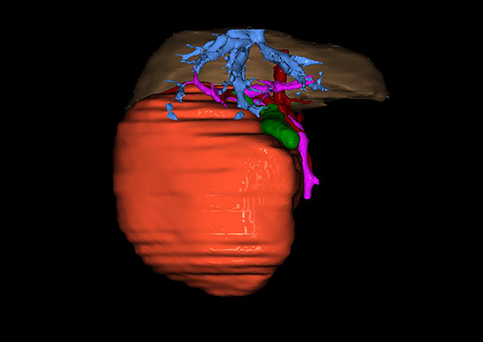

图1 位于肝右的叶肝母细胞瘤, 6个月,男婴

目前常用的检查方法有B超检查、CT、MRI、血管造影等。与其它的腹部肿块的诊断不同,对于小儿肝母细胞瘤血管造影具有重要的意义,可以作为手术前介入治疗的手段,也可为手术提供非常有效的影像学指导,但技术要求高,操作较复杂,且给患儿带来一定的痛苦。近年借助计算机辅助手术系统进行CT原始影像三维重建、手术规划和计算机虚拟手术技术,为精准肝脏手术提供了极为有效的技术支持。